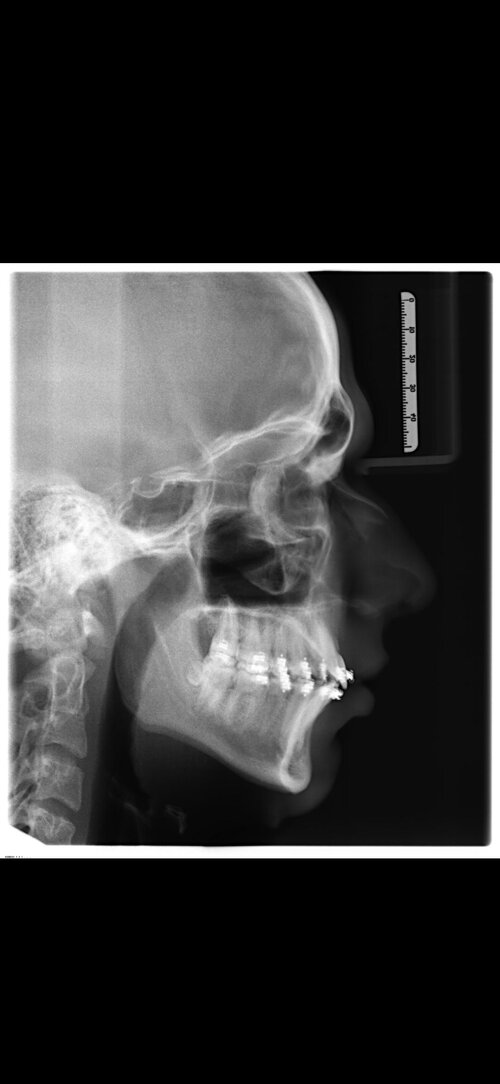

I've already posted a lot about this topic: I'm 17, and i'm getting a bimax surgery + genioplasty and a slight rotation in 7 days performed by Dr Dr Kater (Frankfurt am Main, Germany). I'm paying private, the cause is bad airways and aesthetic problems due to recession in my lower third.

What exactly should i tell him? He's got 35 years of experience and i don't want to sound like a "know-it-all", but i really want a big ascension and i'm scared of underadvancement. Any suggestions what EXACTLY i could tell him and what movements he should perform?